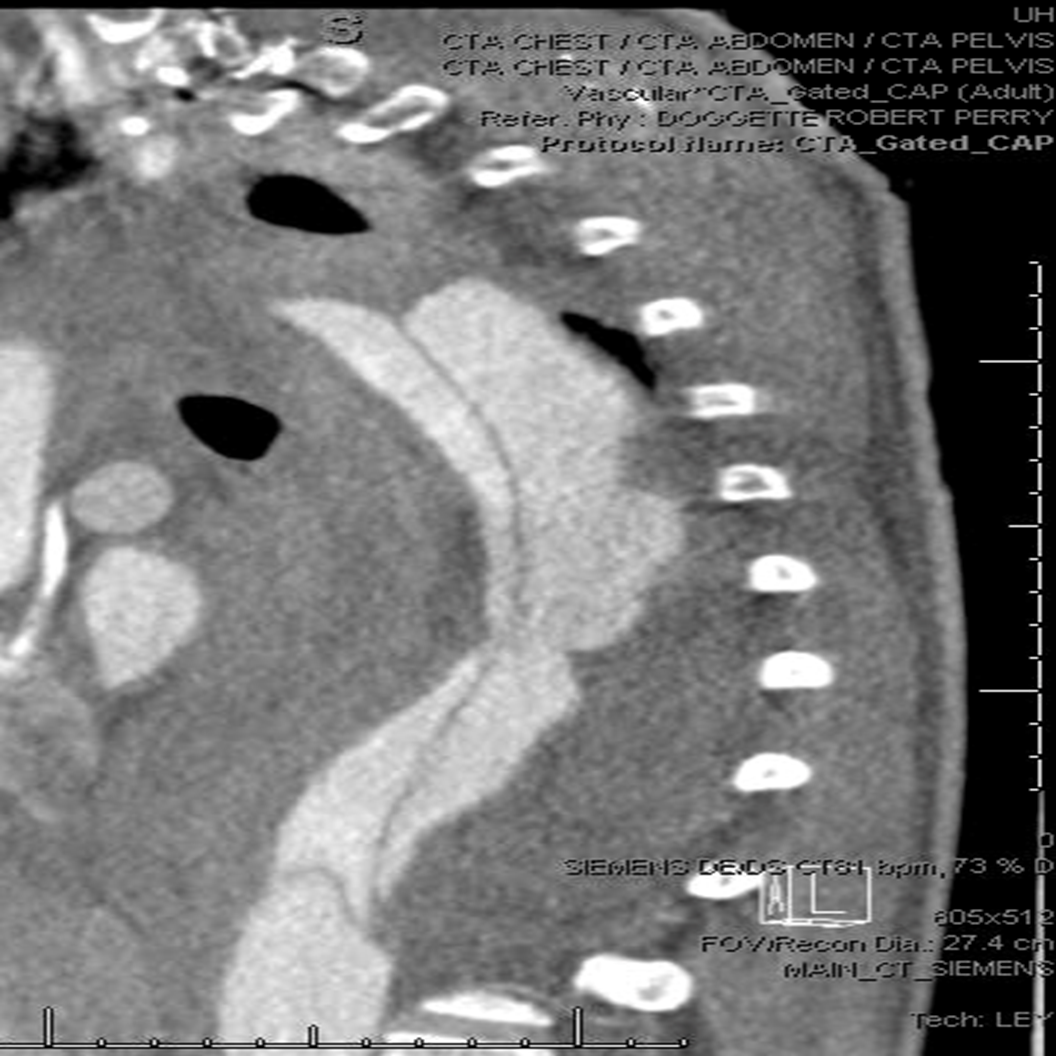

응급실에서 CTA와 심초음파 등 진단 검사를 시행한 결과, B형 대동맥 박리로 판명되었다. B형 박리는 보통 내과적 치료인 약물로 혈압을 조절하는 것이 일반적으로 권장되는 치료방법이고, 혈관외과 컨설트 결과에서도 위험한 수술보다는 약을 통한 내과적 치료를 먼저 권했다.

CTA_Chest.png 자료사진_CTA 영상 소견, 밝은 회색으로 보이는 대동맥 중앙을 지나는 박리가 선명하게 보인다